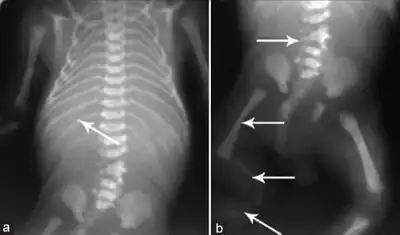

- a) Hypoplastic mandible b)hypoplasia of right lower limb c) dilated urinary bladder asterisk and bilateral hydroureters arrowheads